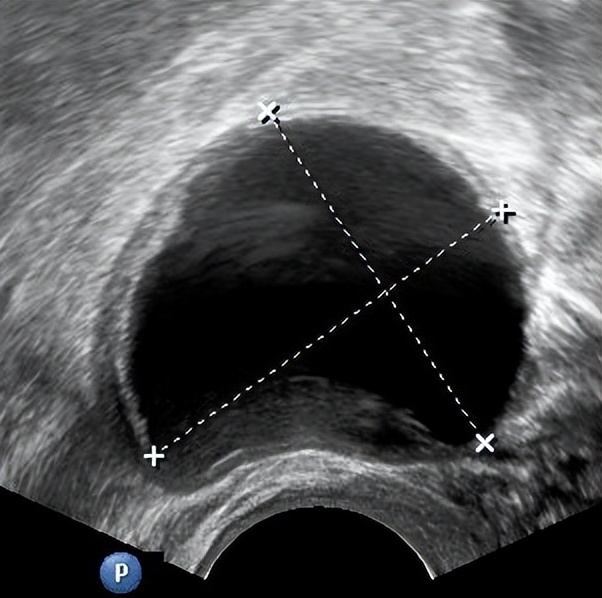

02、 黄体囊肿

卵泡正常排出卵子后,会演变为黄体,正常直径为2~3cm,若黄体内毛细血管出血或液体积聚,则形成黄体囊肿。